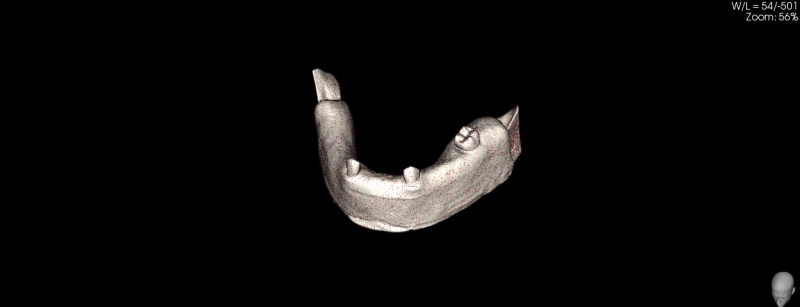

Żuchwa do fantomów z wyrostkiem zębodołowym wyścielonym imitacją błony śluzowej oraz zębami 10-3040

• Żuchwa do fantomów z wyrostkiem zębodołowym wyścielonym imitacją błony śluzowej oraz zębami 10-3040

Żuchwa do fantomów z wyrostkiem zębodołowym wyścielonym imitacją błony śluzowej oraz zębami wraz z ich korzeniami  w pozycji 37, 33, 43 oraz z niezagojonym zębodołem w pozycji 42. W modelu odwzorowano kanały żuchwy i otwory bródkowe. Płytka mocująca umożliwia montaż do większości fantomów znajdujących się na rynku. Model ten można zamontować w dowolnym artykulatorze lub fantomie dentystycznym popularnym na rynku (zalecany manekin to 11-1000).

Poniżej znajduje się przycisk umożliwiający ściągnięcie pliku STL przeznaczonego do wykonanie szablonu do szkoleń implantacyjnych z użyciem modelu.

Numer katalogowy 10-3040